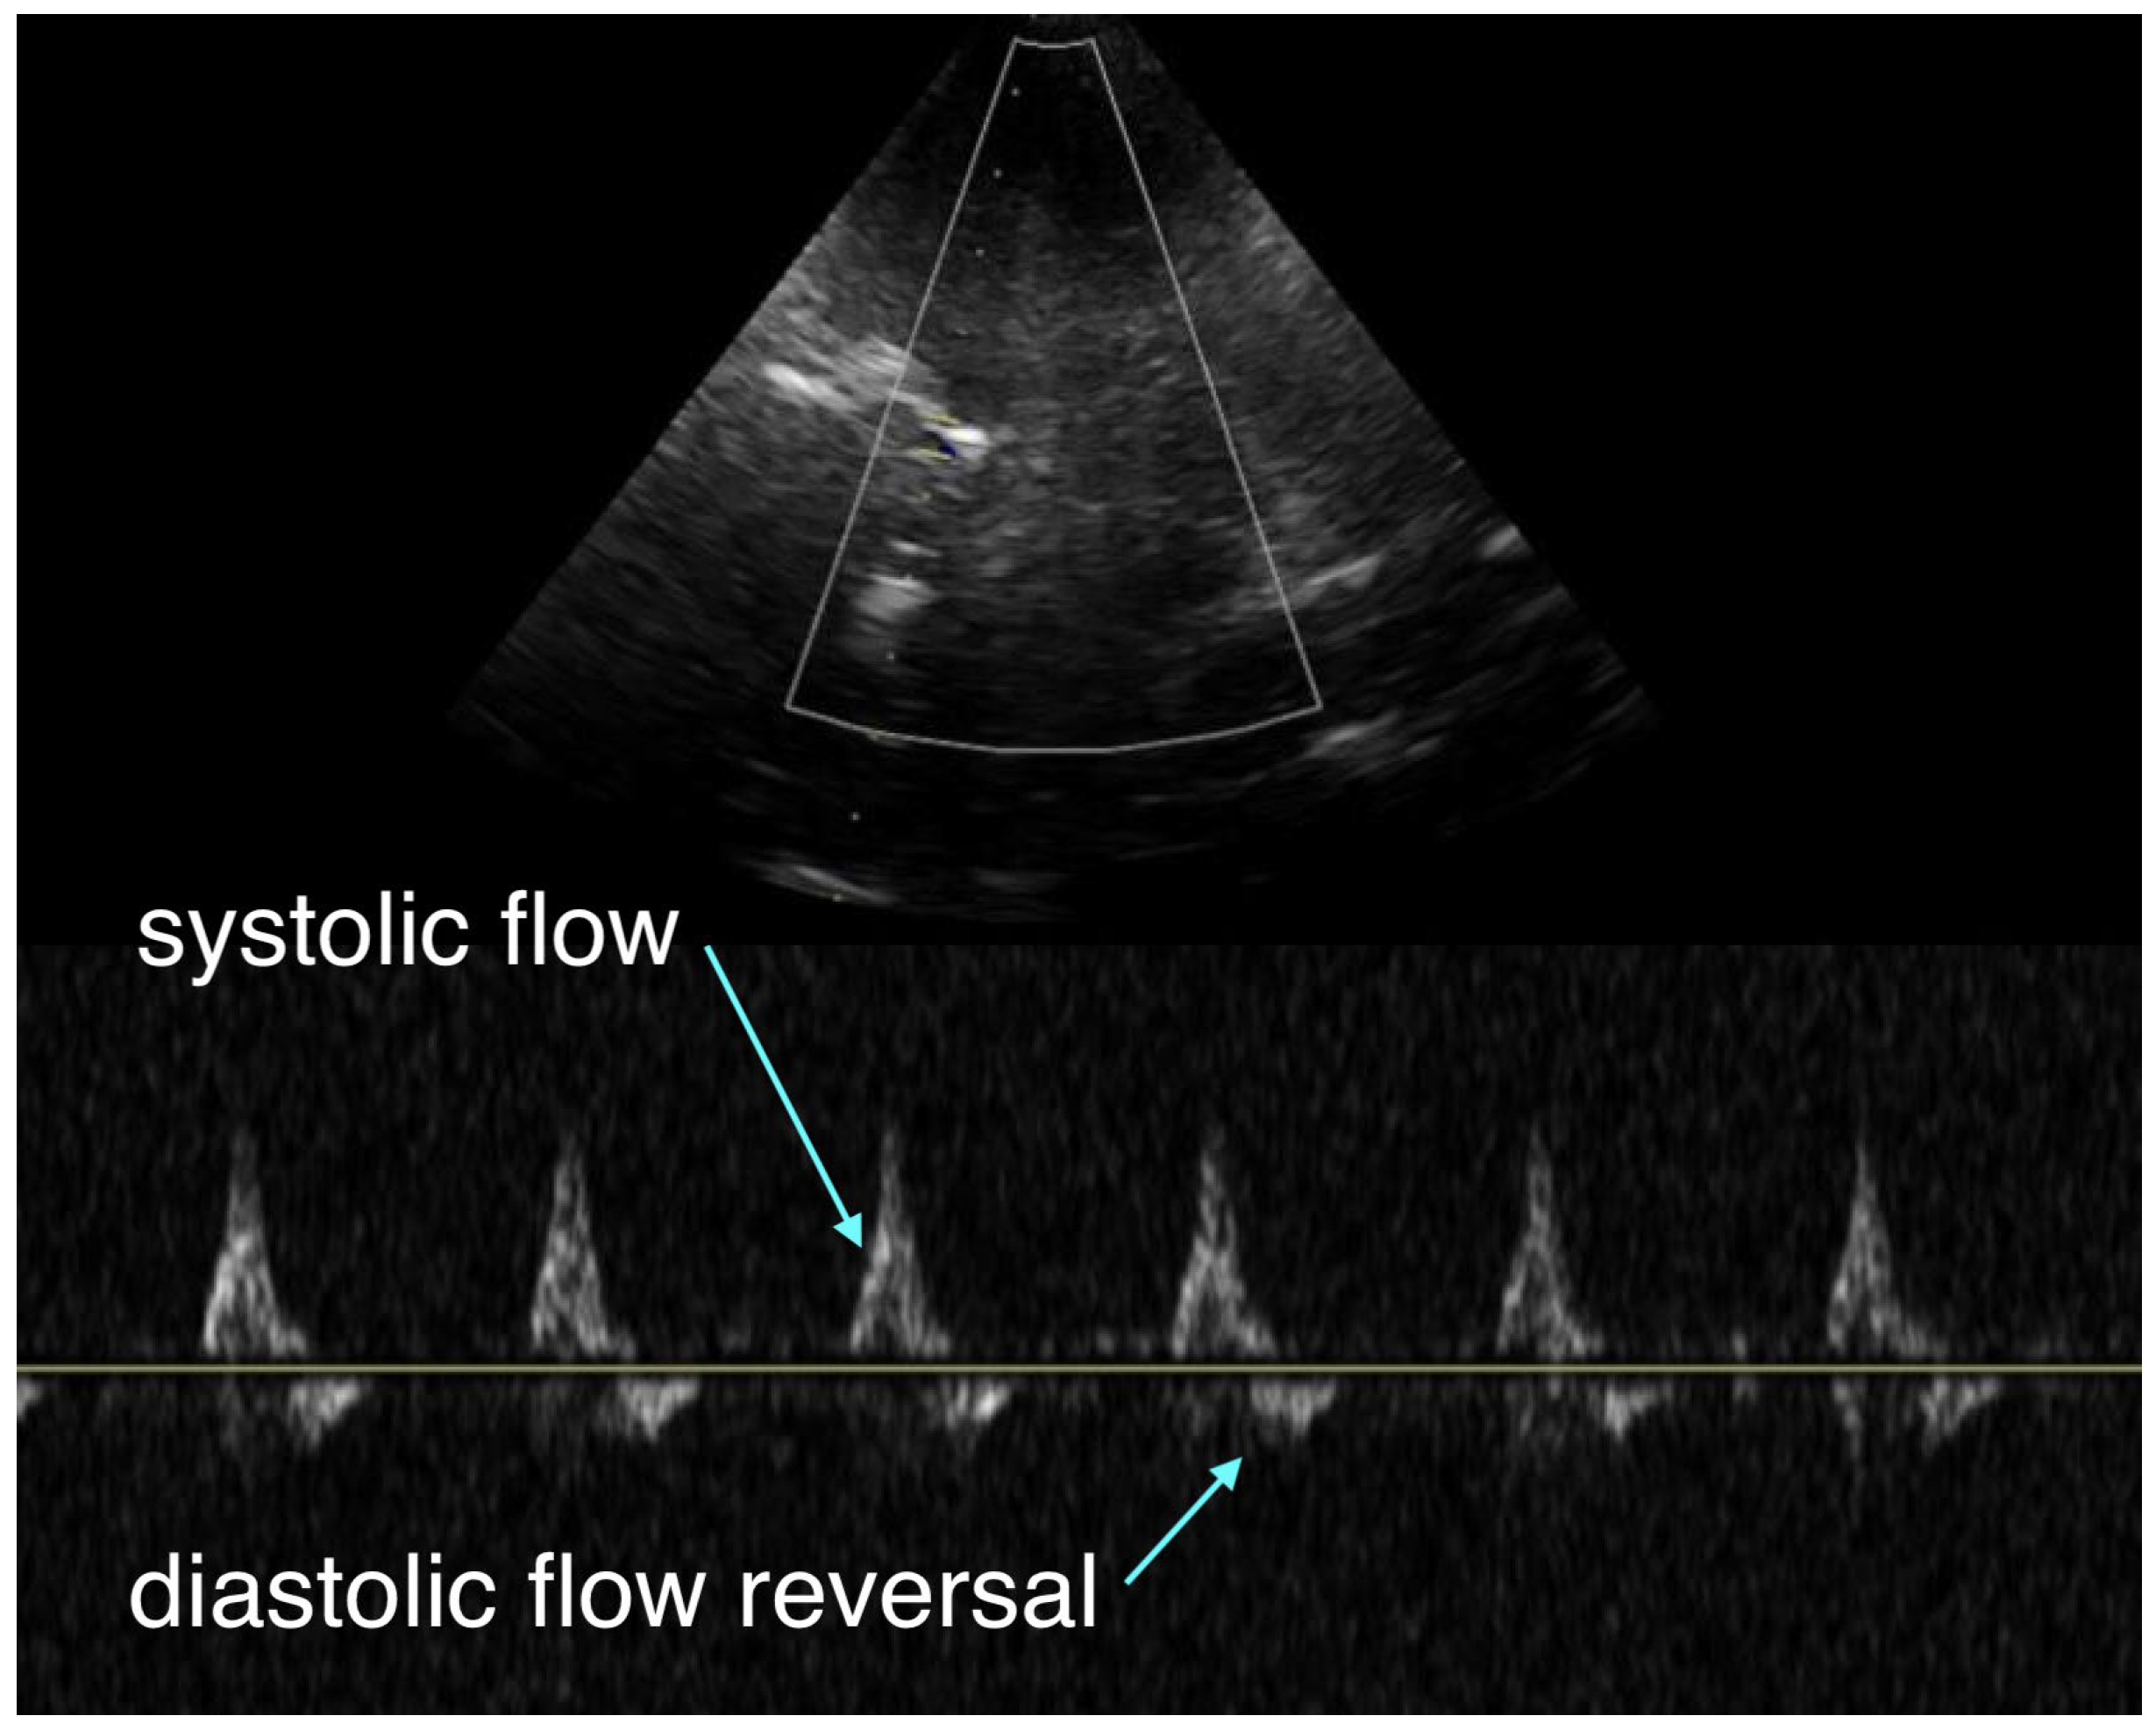

The critical care team arrived and performed resuscitative transesophageal echocardiography (TEE), which confirmed both the adequacy of chest compression positioning with the mechanical compression device (LUCAS) and the absence of left ventricular outflow tract obstruction. The right ventricle was dilated, but no intracardiac thrombus was observed. With no return of spontaneous circulation (ROSC) after a total of 40 minutes of resuscitation, an aortic occlusion catheter (COBRA-OS, Frontline Medical Technologies, London, ON, Canada) was inserted and inflated at approximately 50 minutes of ongoing resuscitation. About five minutes later, TEE demonstrated cardiac activity consistent with pseudo-pulseless electrical activity (pseudo-PEA), with contractions that were largely ineffective and only minimally opened the aortic valve. By that point, the patient had received six milligrams of epinephrine according to ACLS protocol. The tertiary care center providing mechanical circulatory support was then contacted; however, given the prolonged duration of arrest, the additional time required for transfer, and the absence of effective ROSC, the patient was no longer considered a candidate for extracorporeal cardiopulmonary resuscitation (ECPR)

Another important consideration is the potential use of resuscitative TEE as a continuous hemodynamic monitor during the transfer of unstable patients. While definitive outcome studies are still pending, its diagnostic utility is clear: it ensures optimal chest compression positioning and reliably guides the placement of advanced resuscitation cannulae. ([7,8,9]; Figure 2) By contrast, standard inter-hospital transport monitoring is generally limited to an arterial line, non-invasive blood pressure, pulse oximetry, capnography, and a basic transport ventilator, which limits diagnostic capabilities and delays the rapid correction of physiologic abnormalities.

Figure 2. Our team uses trans-esophageal thoracic ultrasound to ascertain appropriate guidewire placement in the thoracic aorta and to monitor appropriate balloon inflation and position.